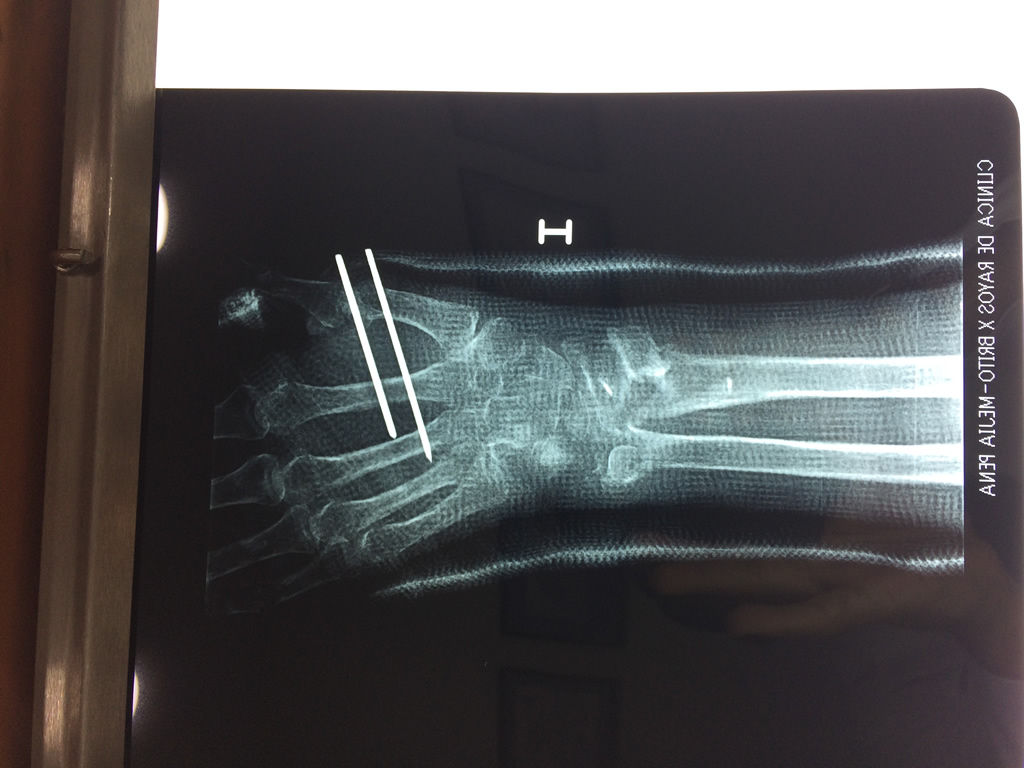

Los procedimientos más comunes en cirugía de la mano son aquellos destinados a reparar traumatismos, incluyendo lesiones de tendones, nervios, vasos sanguíneos, y articulaciones; huesos fracturados; y quemaduras, cortes, y otros daños de la piel.